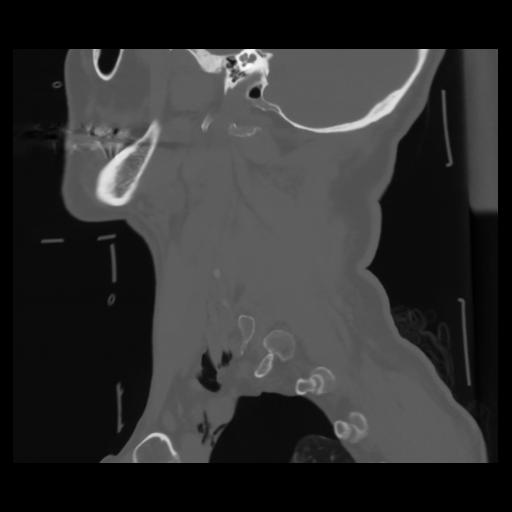

14 P.BLANDAS,,Sagittal,2.000,P.BLANDAS,Sagittal,